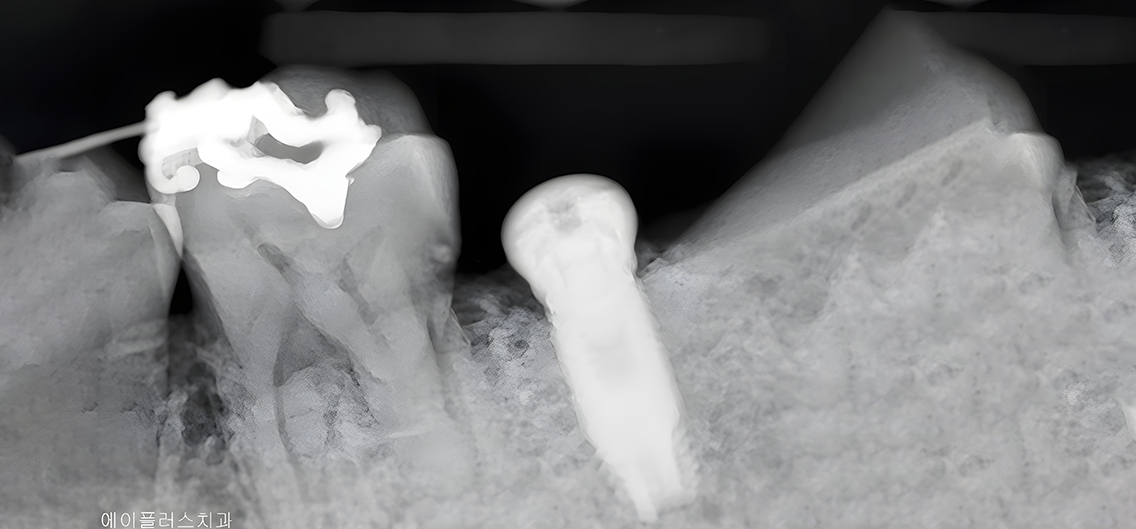

정밀 CT 촬영과 구강 검사를 통해 잇몸·뼈 상태를 확인하고, 개인에게 가장 적합한 임플란트 치료 계획을 세웁니다.

치조골에 임플란트 픽스처(뿌리 역할)를 정확하게 심는 단계로, 국소마취 하에 안전하게 진행됩니다.

A+ 임플란트의 다양한 케이스를 확인해보세요.